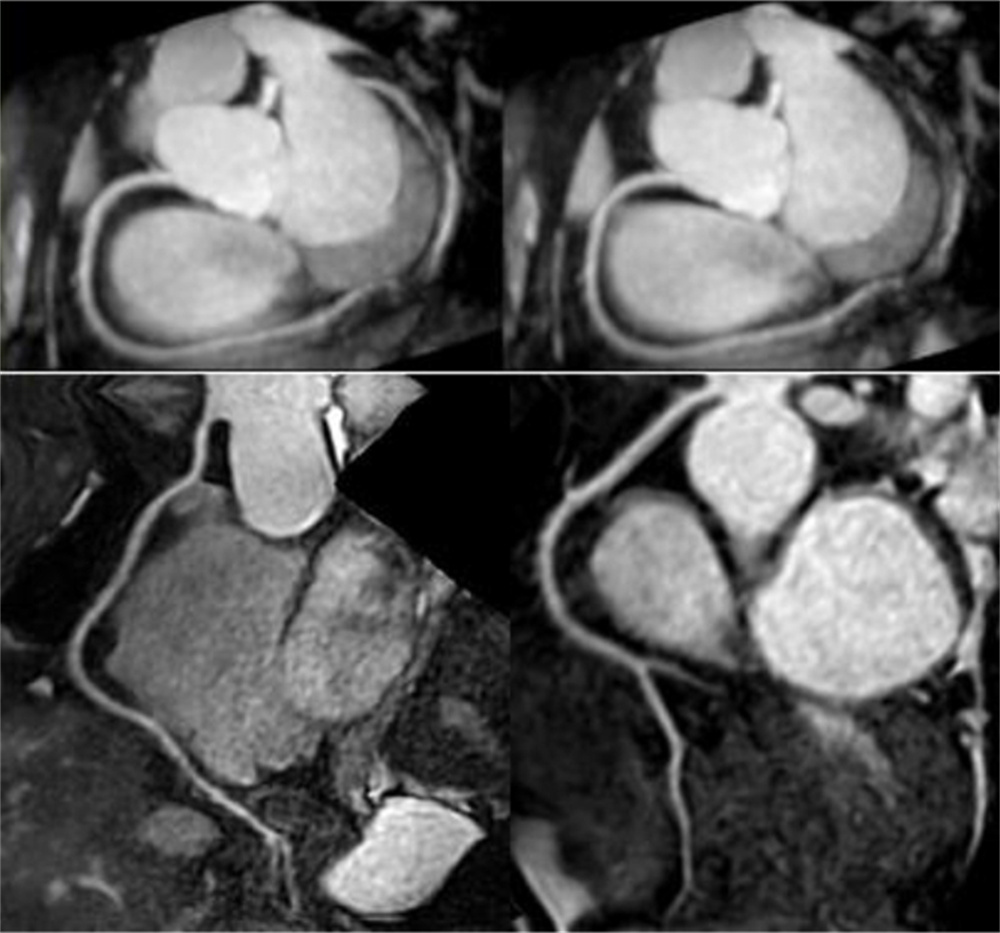

飞利浦大孔径光速Ingenia 3.0T磁共振是业内唯一同时具备"全数字高清成像平台和四维多源射频发射成像平台"的高端3T磁共振,具有病人检查舒适,扫描速度快,图像分辨率高的特点。在神经系统,骨肌系统,体部系统包括心脏和腹部等都有良好的应用和独到优势,为疾病的诊断及治疗提供更可靠、更丰富的信息,对于脑卒中和胸痛等中心的建设起到重要的作用。设备具备飞利浦独有的全数字线圈,可以实现三维全心不打药冠脉成像,无电离辐射和造影剂过敏风险,精准显示冠脉狭窄,有效排查临床无意义的冠脉狭窄(准确度达90%)。

磁共振冠状动脉检查无辐射,无需对比剂,对于缺血性心脏病,可以一次成像完整显示全心冠脉,便于直观诊断冠脉各分支情况。